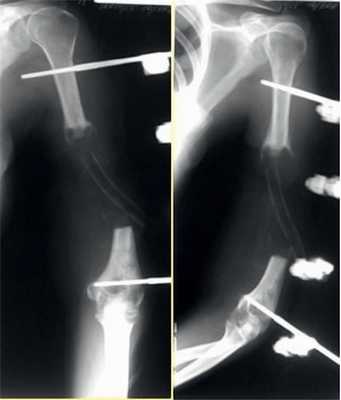

Пациентка Н., 41 года.

Диагноз: ложный сустав левой плечевой кости.

На рис. 10-14 Рис. 10. Рентгенограмма пациентки Н. до операции. Рис. 14. Внешний вид и функция пациентки Н. через 8 мес после операции. представлены этапы обследования и лечения пациентки Н.

Рис. 11. Пациентка Н. Оперативное лечение: резекция зоны ложного сустава левой плечевой кости, остеосинтез пластиной и винтами. Пластика свободным кровоснабжаемым трансплантатом из внутреннего мыщелка бедренной кости.

Рис. 12. Рентгенограммы пациентки Н. после операции.

Рис. 13. Рентгенограммы пациентки Н. через 8 мес после операции.